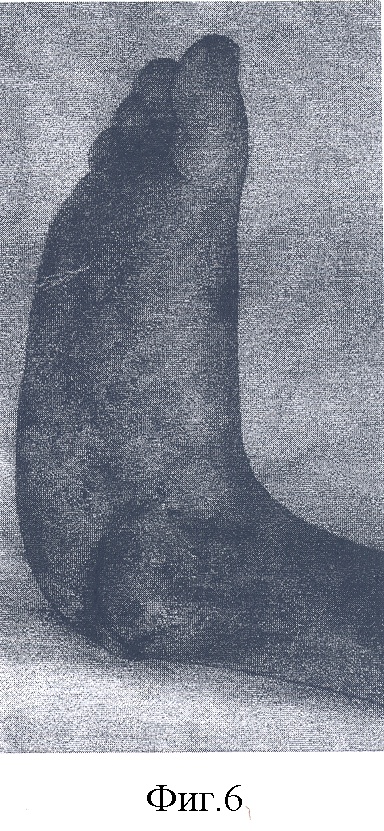

– на фиг.5, 6 – анатомический результат пластики таранной и пяточной костей правой стопы;